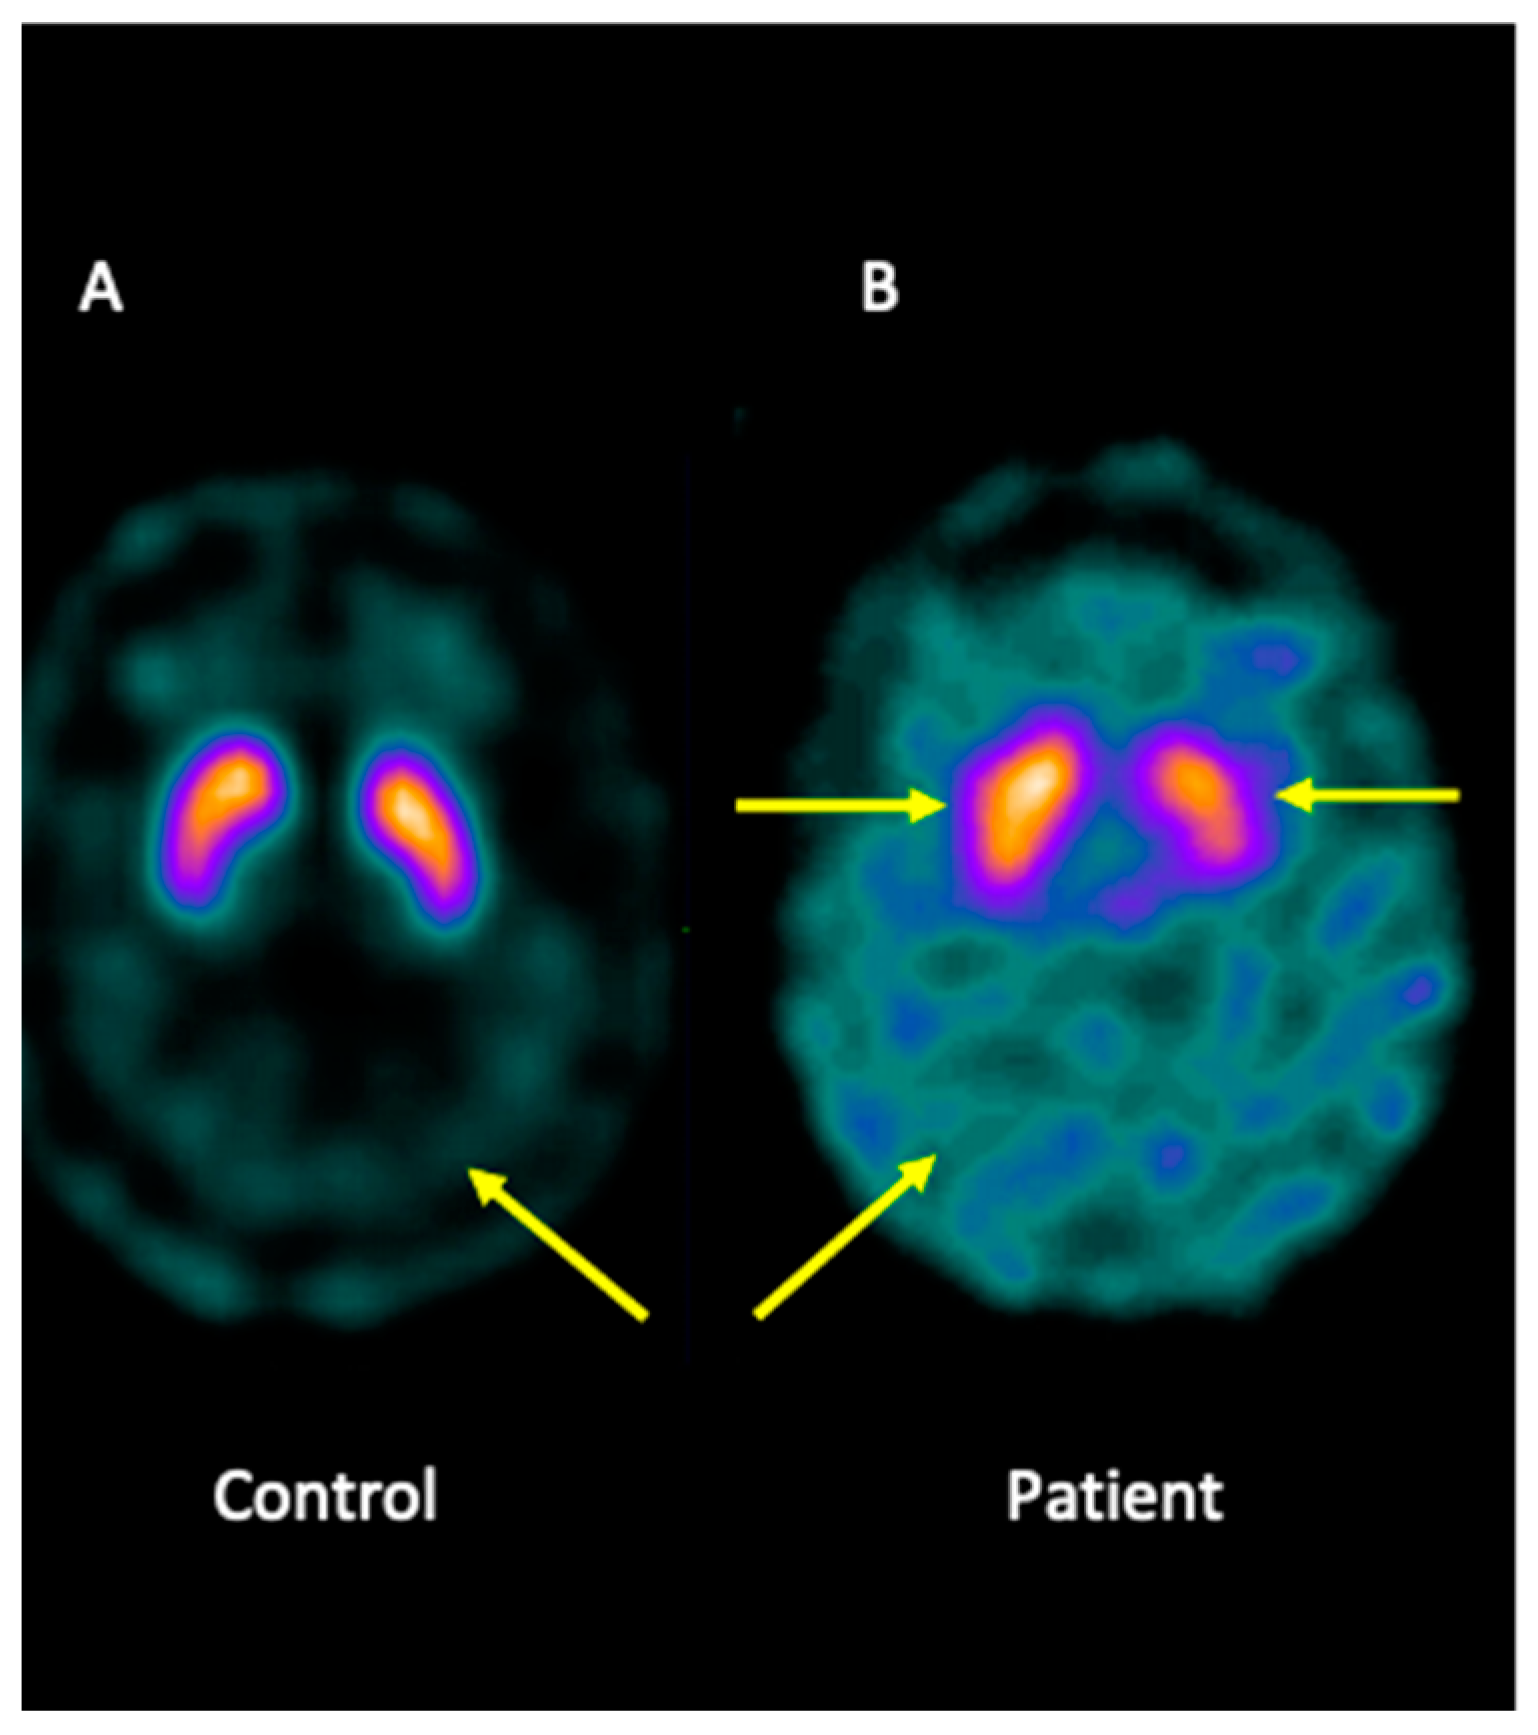

4.2. Analysis of the Brain Imaging with Single-Photon Emission Computed Tomography